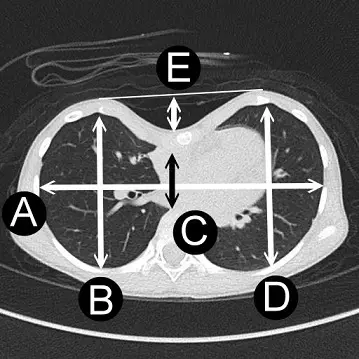

Haller index或稱凹陷指數,常用於漏斗胸(pectus excavatum)的嚴重度評估,是由Dr. Haller等人在1987年所提出來的方法,圖中A為白色橫向雙箭頭線長度;B、D分別為左右兩側白色縱向雙箭頭線長度;C為中間黑色縱向雙箭頭線長度;E為中間白色縱向雙箭頭線長度,則Haller index為何?

Haller 指數 (Haller index) 定義為胸腔最寬內側肋緣間距離(即圖中 A)與胸骨最凹點至脊椎前表面最短距離(即圖中 C)之比值,因此正確答案為 A/C,對應選項 A。